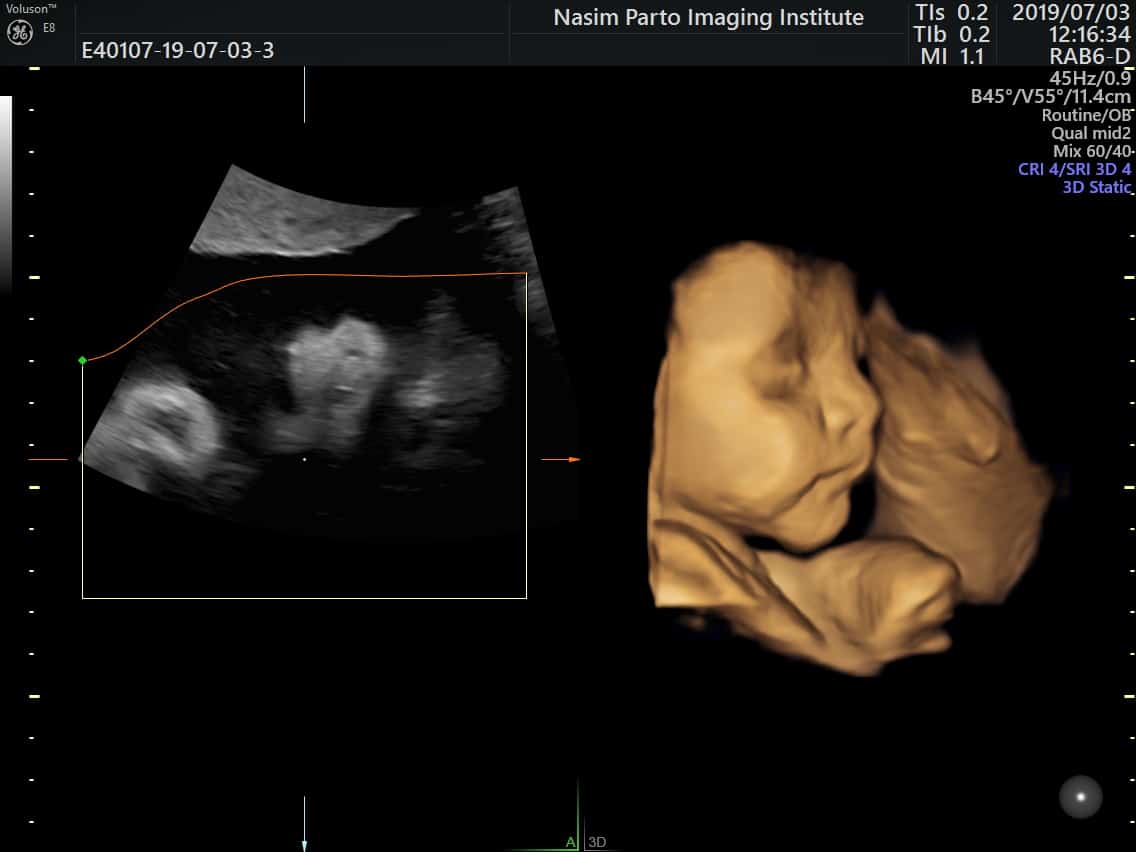

در اسکن 20 هفته ای، احتمالاً ضربان قلب کودک، انحنای ستون فقرات، صورت نوزاد و تکان دادن دست ها و پاهای او را خواهید دید. حتی ممکن است یک مکیدن انگشت زیبا هم وجود داشته باشد.

معمولاً می توانید یک عکس اولتراسوند یا حتی یک DVD برای به اشتراک گذاشتن با خانواده و دوستان دریافت کنید. برخی از خدمات دارای اسکنر اولتراسوند سه بعدی یا حتی چهار بعدی هستند، اما این اسکن ها اغلب هزینه اضافی دارند.

تصاویری از یک نوزاد را به صورت 3 بعدی/4 بعدی نشان دهید

در اسکن آناتومی و ناهنجاری 20 هفته ای، می توانید بدن، بازوها، پاها، انگشتان دست، انگشتان پا و ویژگی های صورت کودک خود را ببینید. متخصص سونوگرافی شما آناتومی کودک شما را بررسی می کند و اندام های داخلی را بررسی می کند و از طریق تصاویر روی صفحه با شما صحبت می کند. اگر اندام تناسلی پوشیده نیست و می خواهید بدانید، می توانیم جنسیت نوزادتان را به شما بگوییم. پس از قرار ملاقات شما، یک لینک امن برای شما ارسال می کنیم که می توانید مجموعه ای از تصاویر را از اسکن خود مشاهده و دانلود کنید.

چه انتظاری داشته باشید شما با متخصص سونوگرافی پیش از تولد یا پزشک متخصص در تشخیص قبل از تولد ملاقات خواهید کرد. اسکن واقعی حدود 30 دقیقه طول می کشد و در این مدت می توانید تصاویر سه بعدی کودک خود را روی صفحه ببینید. لطفاً یک ساعت برای قرار خود وقت بگذارید تا عجله نکنید و بتوانید سؤال بپرسید.

در مرکز الوند، سونوگرافی آنومالی با بهرهگیری از دستگاههای پیشرفته سهبعدی و چهاربعدی انجام میشود. در این روش، پزشک متخصص سونوگرافی با قرار دادن پروب بر روی شکم مادر و استفاده از ژل مخصوص، تصاویر دقیقی از جنین دریافت میکند.